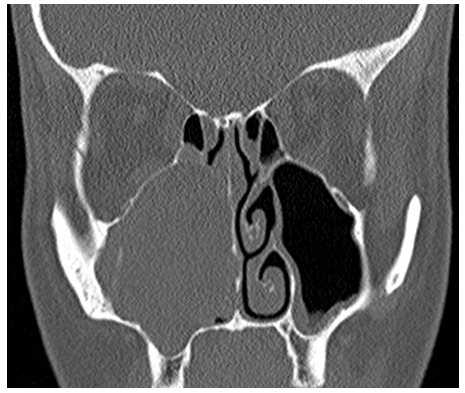

A 39year old Caucasian female presented with a few years history of progressive right sided nasal blockage with no associated history of epistaxis, headache or pain. She was a non-smoker and otherwise fit and well. On examination, there was decreased air entry on the right side. Nasal endoscopy revealed a straight nasal septum but the right nasal cavity was smaller compared to the left side. Endoscopically, no intranasal lesion was identified but because of the bulge in the right lateral nasal wall, a computed tomogram (CT) of her paranasal sinuses was arranged. The CT scan revealed soft tissue opacity in the right maxillary sinus with expansion of the sinus into the right nasal cavity but no evidence of bony erosion (Figures 1&2).

Figure 2 CT scan shows complete opacification of the right maxillary sinus and nasal cavity.